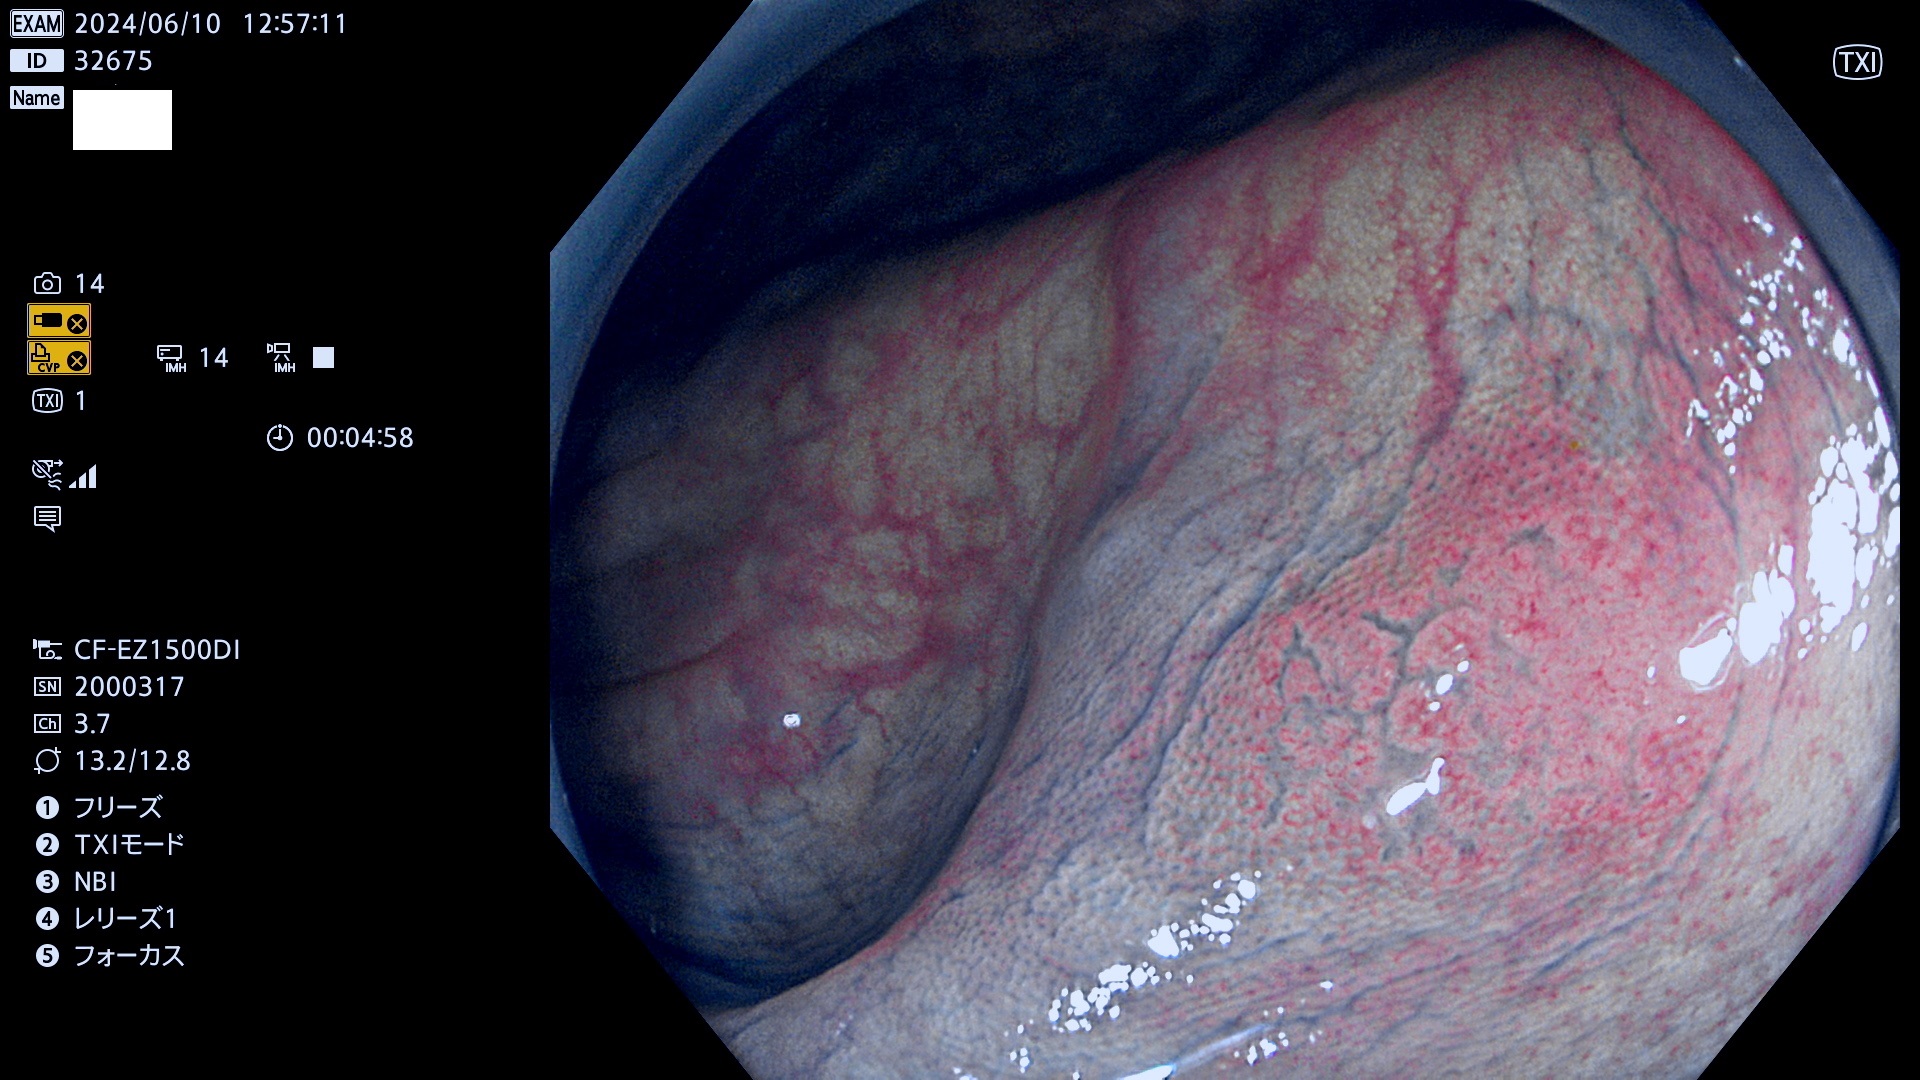

今週のUb、Uc型腺腫

表面型腺腫(Flat Adenoma)の中で、完全に平坦な物をUb、陥凹している物をUcと呼びます。平坦隆起型(Ua)よりも、発見が難しく危険な病変です。

毎週の検査(木・金・土・日)に発見されたUb、Uc型・腺腫を、その週の日曜の夜にUPし1週間、提示します。

抽出の対象期間 2024年6月6日〜6月10の5日間(50件の検査)7件 (7/50=14%)